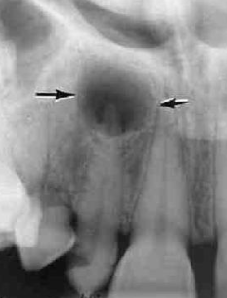

Radiographic Adjacent Structures : radiolucent lesion that extends between the roots, as seen in a traumatic bone cyst (TBC)

scalloping